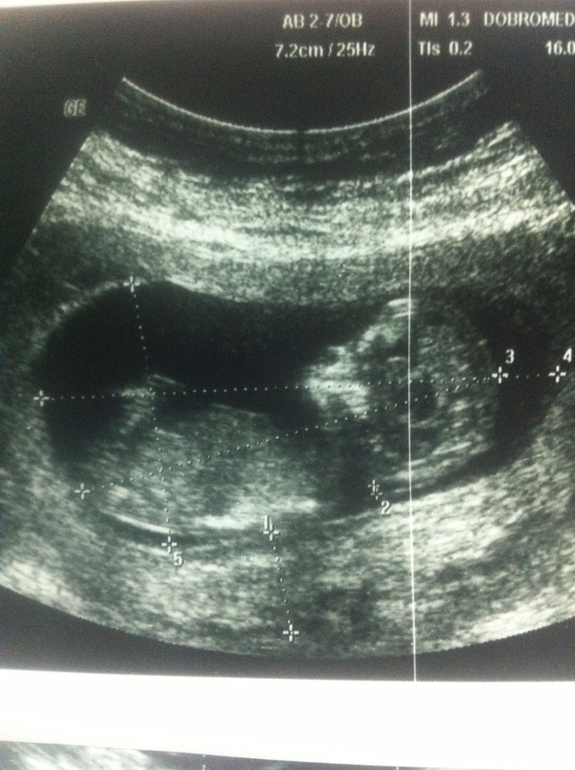

вот сегодня повторно была на скрининге: КТР 65,3; БПР 23,0; .ТВП 1,8

58 мм КТР и насчитали 12.6? Очень странно. Вообще должно быть меньше. Я проходила скрининг в 12.4 недели, КТР 65.3 и это на 12.6 недель. В первую беременность УЗИ было в 12.3 недель КТР 52.3 на 11.6 недель

У меня в первую в 12 н 4 д КТР был 62 мм, написали 12 н 4 д.

А в эту в 12 н 2 дн был 67 мм, но в эту сказали, что мы на 13 недель ровно.